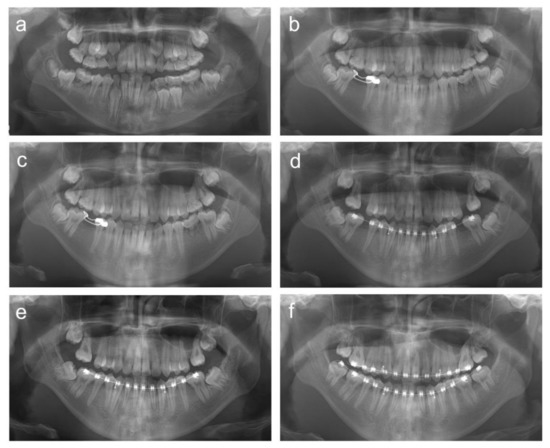

2.1. Case 1

2.2. Case 2

2.3. Case 3

2.4. Case 4

2.5. Case 5